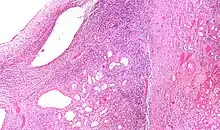

| Micrograph of a cystic nephroma (left of image). Normal kidney is seen on the right. H&E stain. | |

A cystic nephroma, also known as multilocular cystic nephroma, mixed epithelial stromal tumour (MEST) and renal epithelial stromal tumour (REST),[1] is a type of rare benign kidney tumour.

High magnification micrograph of a cystic nephroma showing the characteristic simple epithelium with hobnail morphology, and the ovarian-like stroma. H&E stain.

The characteristics of cystic nephromas are:

- Cysts lined by a simple epithelium with a hobnail morphology, i.e. the nuclei of the cyst lining epithelium bulges into the lumen of the cysts,

- Ovarian-like stroma that has a:

- Spindle cell morphology, and has a

- Basophilic cytoplasm.